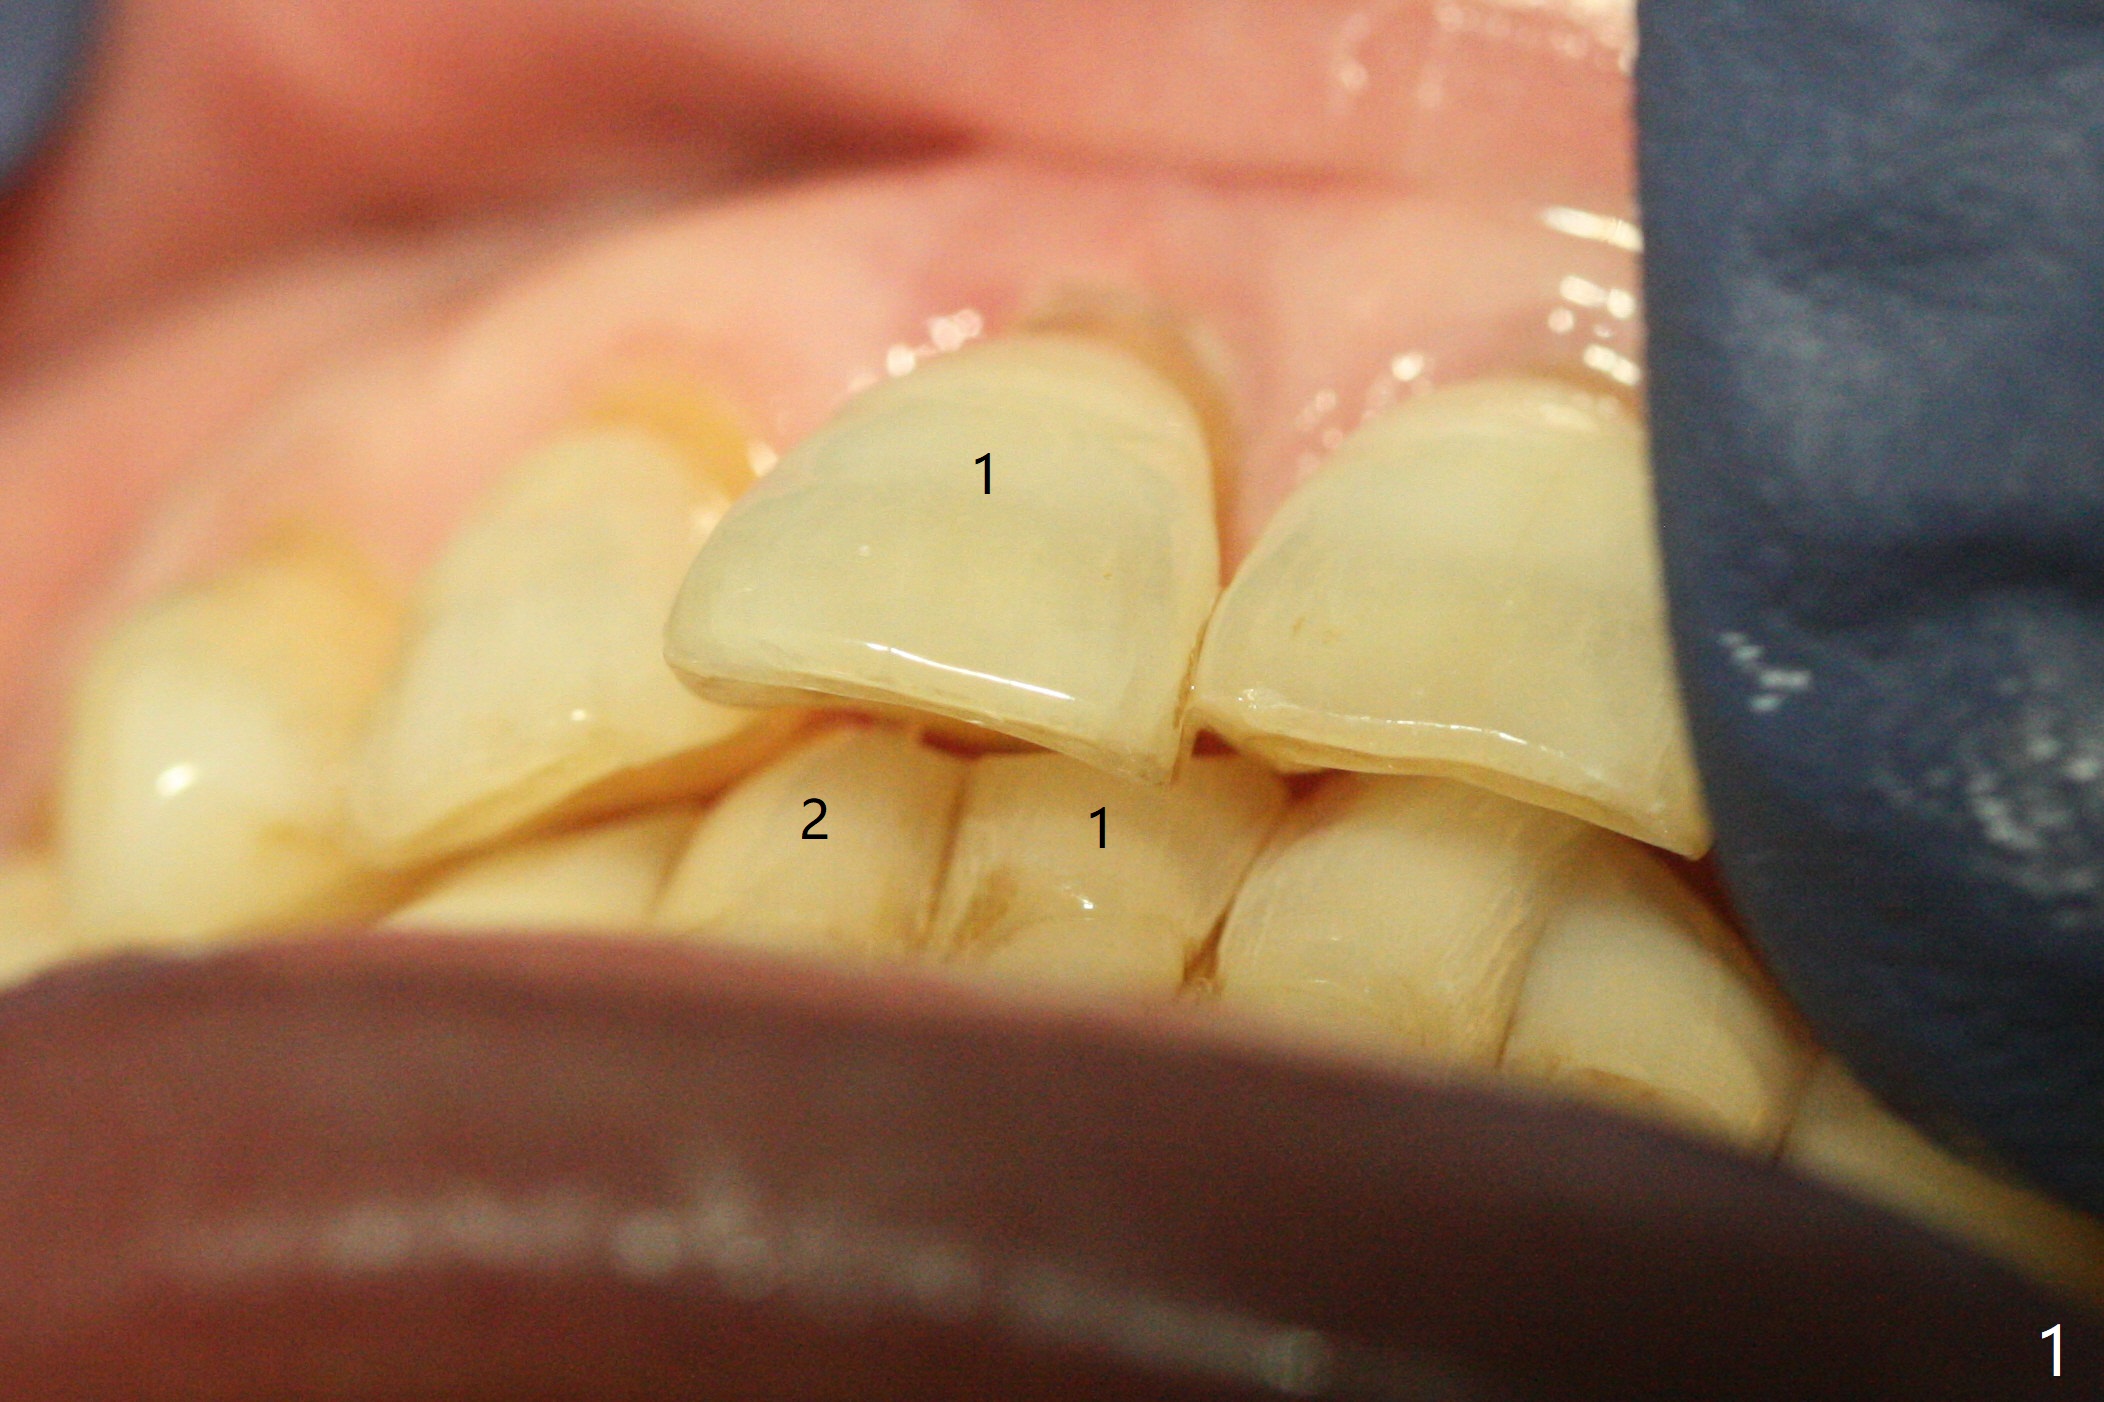

59岁女术前右下1,2切缘磨短后,右上1颊侧移位得到纠正(图一(咬合创伤))。拔牙后证实颊侧骨板缺失,钻洞始于腭侧(图二),当1.5毫米钻头感觉刚穿破鼻底时,置入2.5x14(4)毫米一段式植体,好像进入鼻腔,但是扭力<10Ncm(图三)。把一张PRF膜放入牙槽窝,一端紧贴颊侧牙龈腭侧,另一端放置颊侧牙龈颊侧(图四),然后开始用粘性骨粉(图五,七:*(100%皮质骨))充填颊侧间隙。后者填满时(图五:*),将外面一端PRF翻转覆盖牙槽窝开口,并插入基台固定(图六),最后插入龈下,用临时牙冠固定(图八(T),九(*:PRF))。术后九天牙龈退缩(图十:^),临时牙冠突出(*),后者龈缘和切缘进行调整,缩短(图十一,十二),少许骨粉暴露(图十二:>),十四天后牙龈往下生长,好像形成角化龈(图十三:*)。